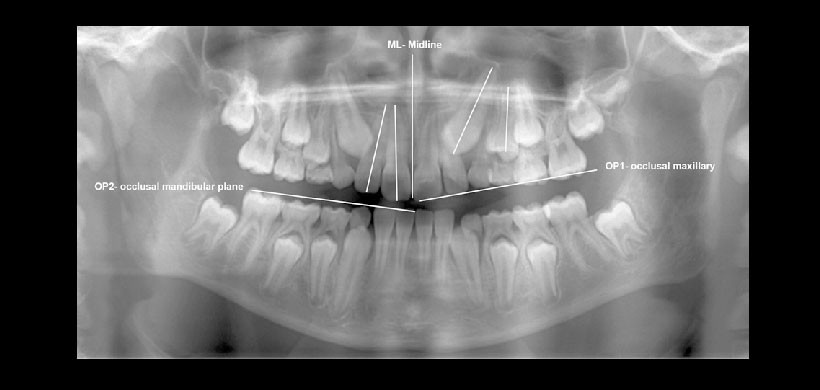

Fig 1. Manera correcta de trazar los ejes longitudinales de los dientes, nótese que va desde el eje radicular hacia el eje coronal de la línea media, Se observa la correcta visualización de los planos oclusa.es y de la línea medio sagital.

Fig 2. Manera de cómo realizar las mediciones angulares y lineales. Si la angulación del canino con el del primer premolar es mayor al valor normal, entonces hay mayor probabilidad de impactación; Si las distancias entre la cúspide del canino con la línea media sagital es menor o la distancia entre la cúspide y el plano de oclusión es mayor a los valores normales entonces existirá mayor predicibilidad de impactación.